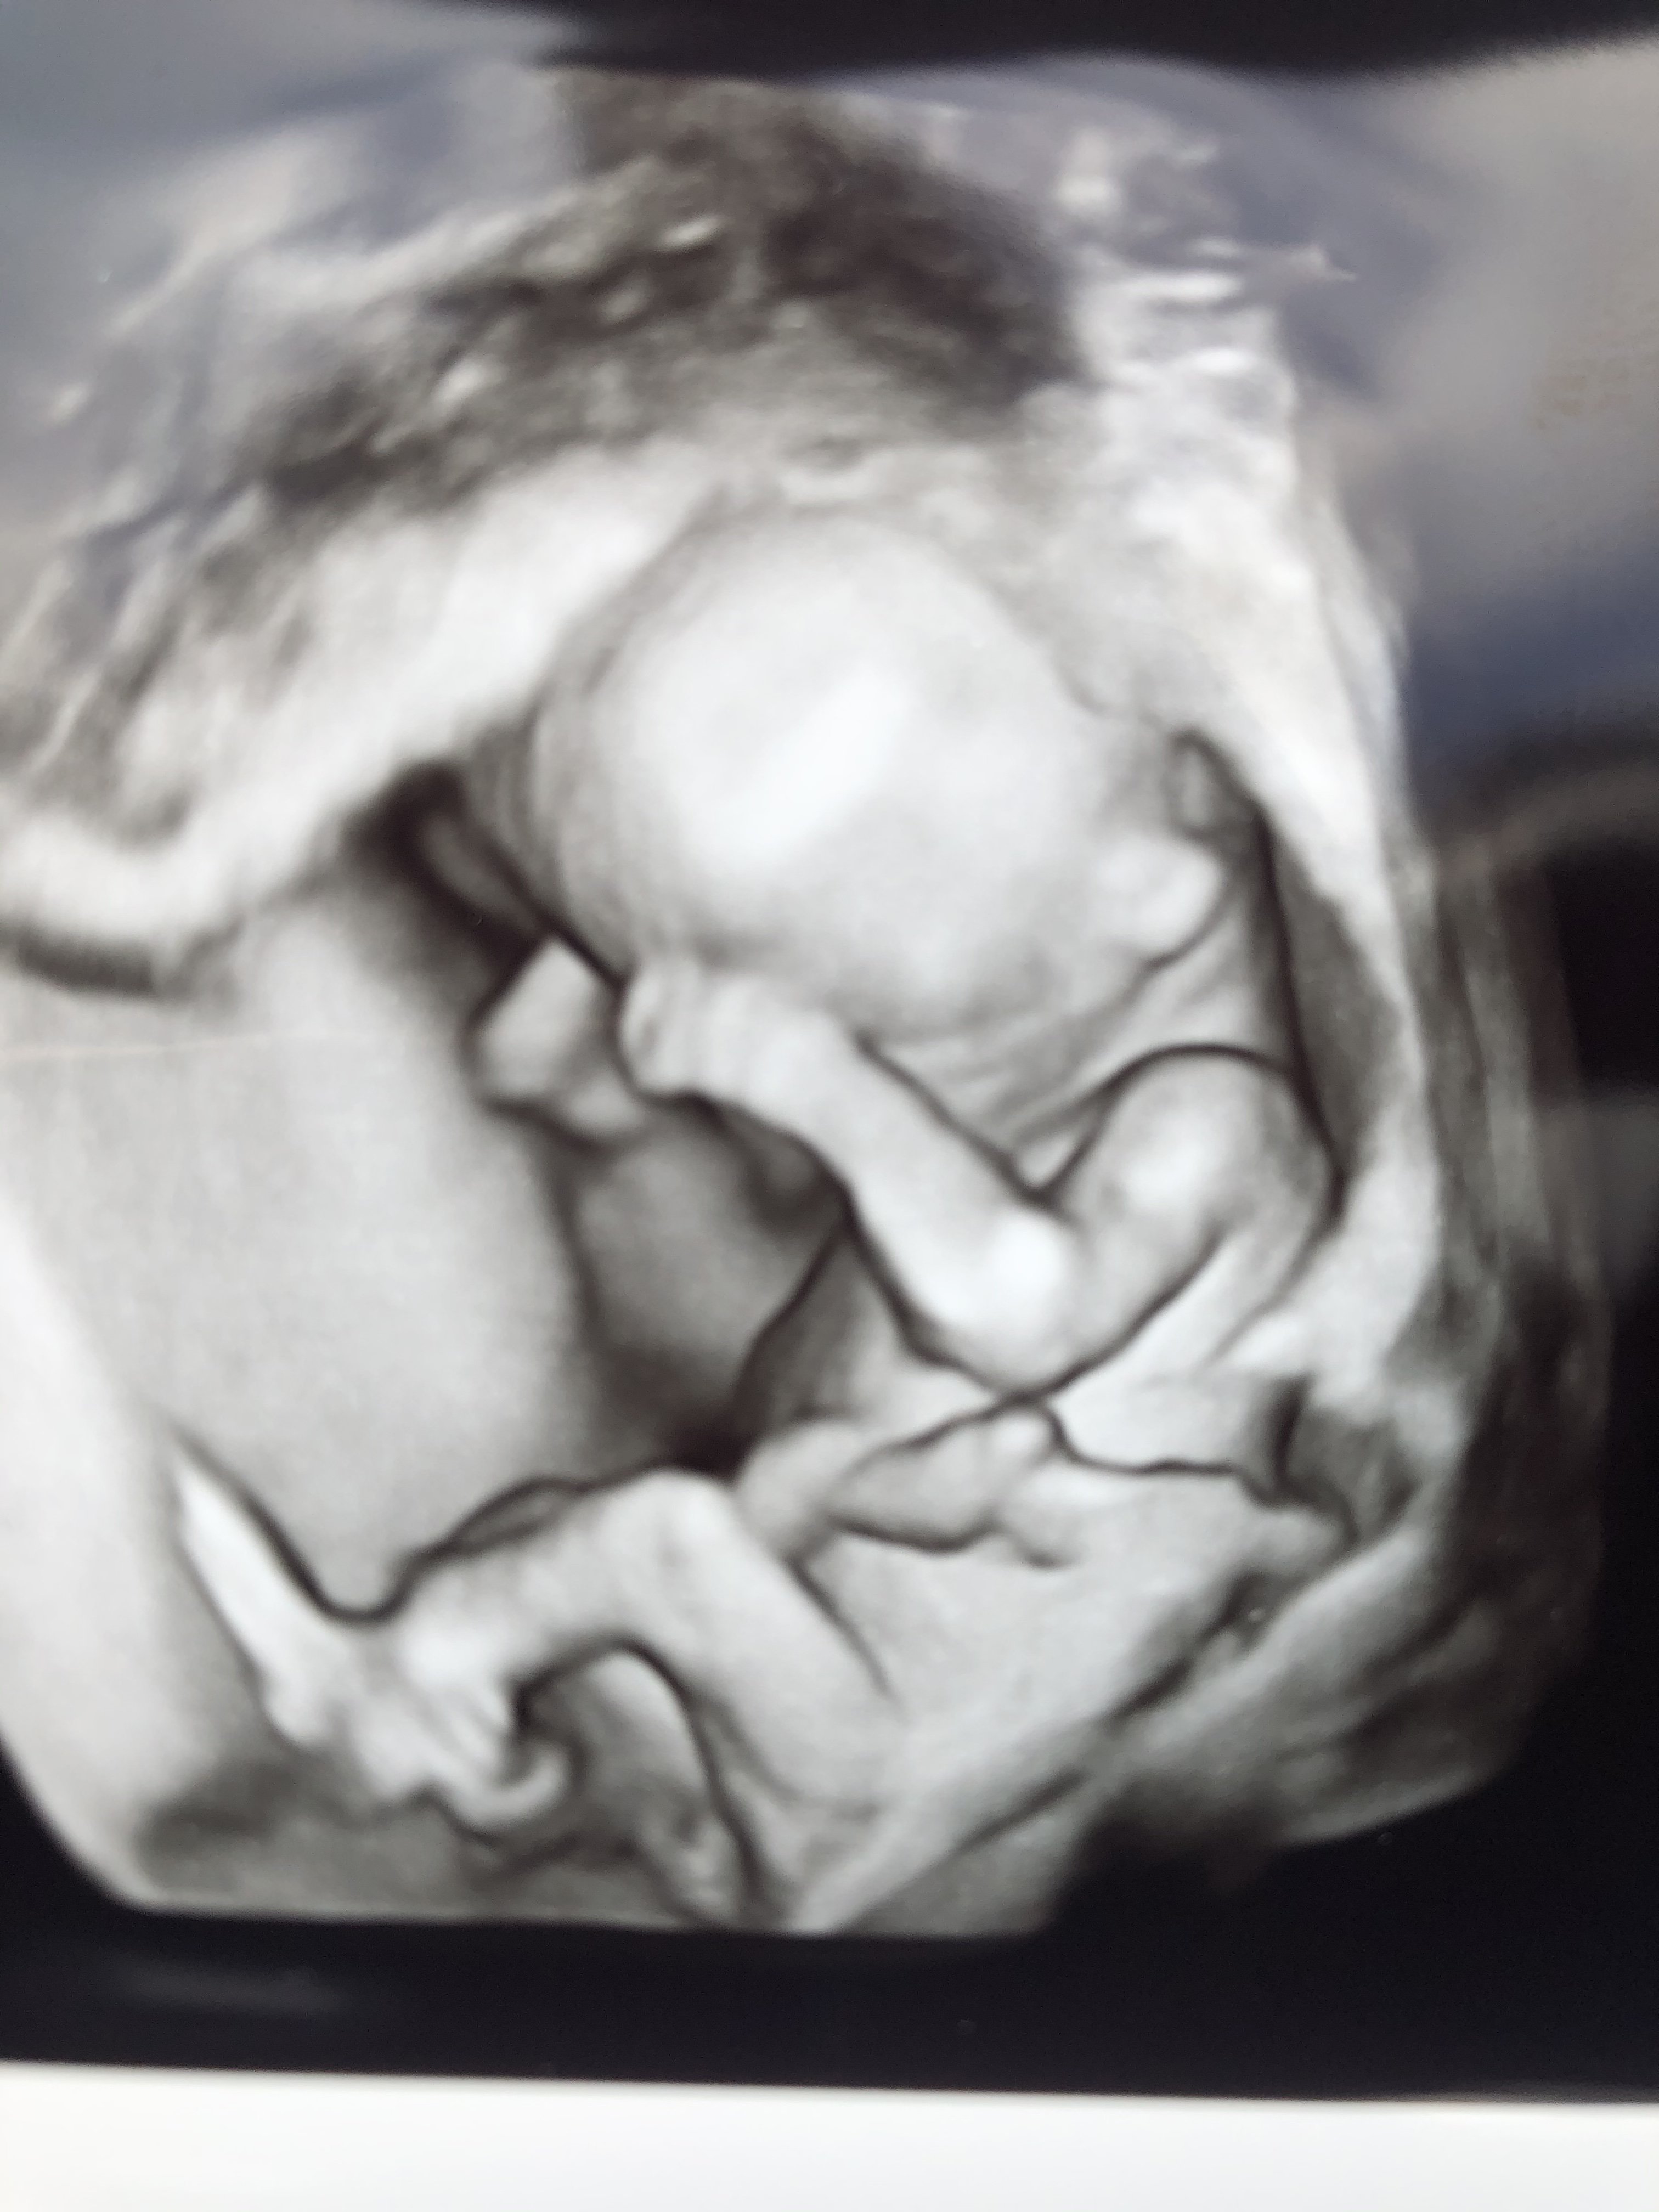

A to przezierność miałaś robiona jako prenatalne czy po prostu na USG? Właśnie nie wiem czy się dobrze zrozumiałam z lekarzem bo powiedziałam że chciałabym zrobić prenatalne USG i powiedział że zrobimy. I nie wiem czy po prostu zrobi mi zwykle badanie czy sprawdzi wszystko tak jak na prenatalnych kark, nos, itpWszystko dobrze, dzidzia ma prawie 5cm. Termin porodu wg usg i wg miesiączki taki sam. Dzidzia ssała kciuk. Jeszcze nie wiem czy dziewczynka czy chłopiec. Czekam na prenatalne 7.09. ale przezierność karkowa w normie.